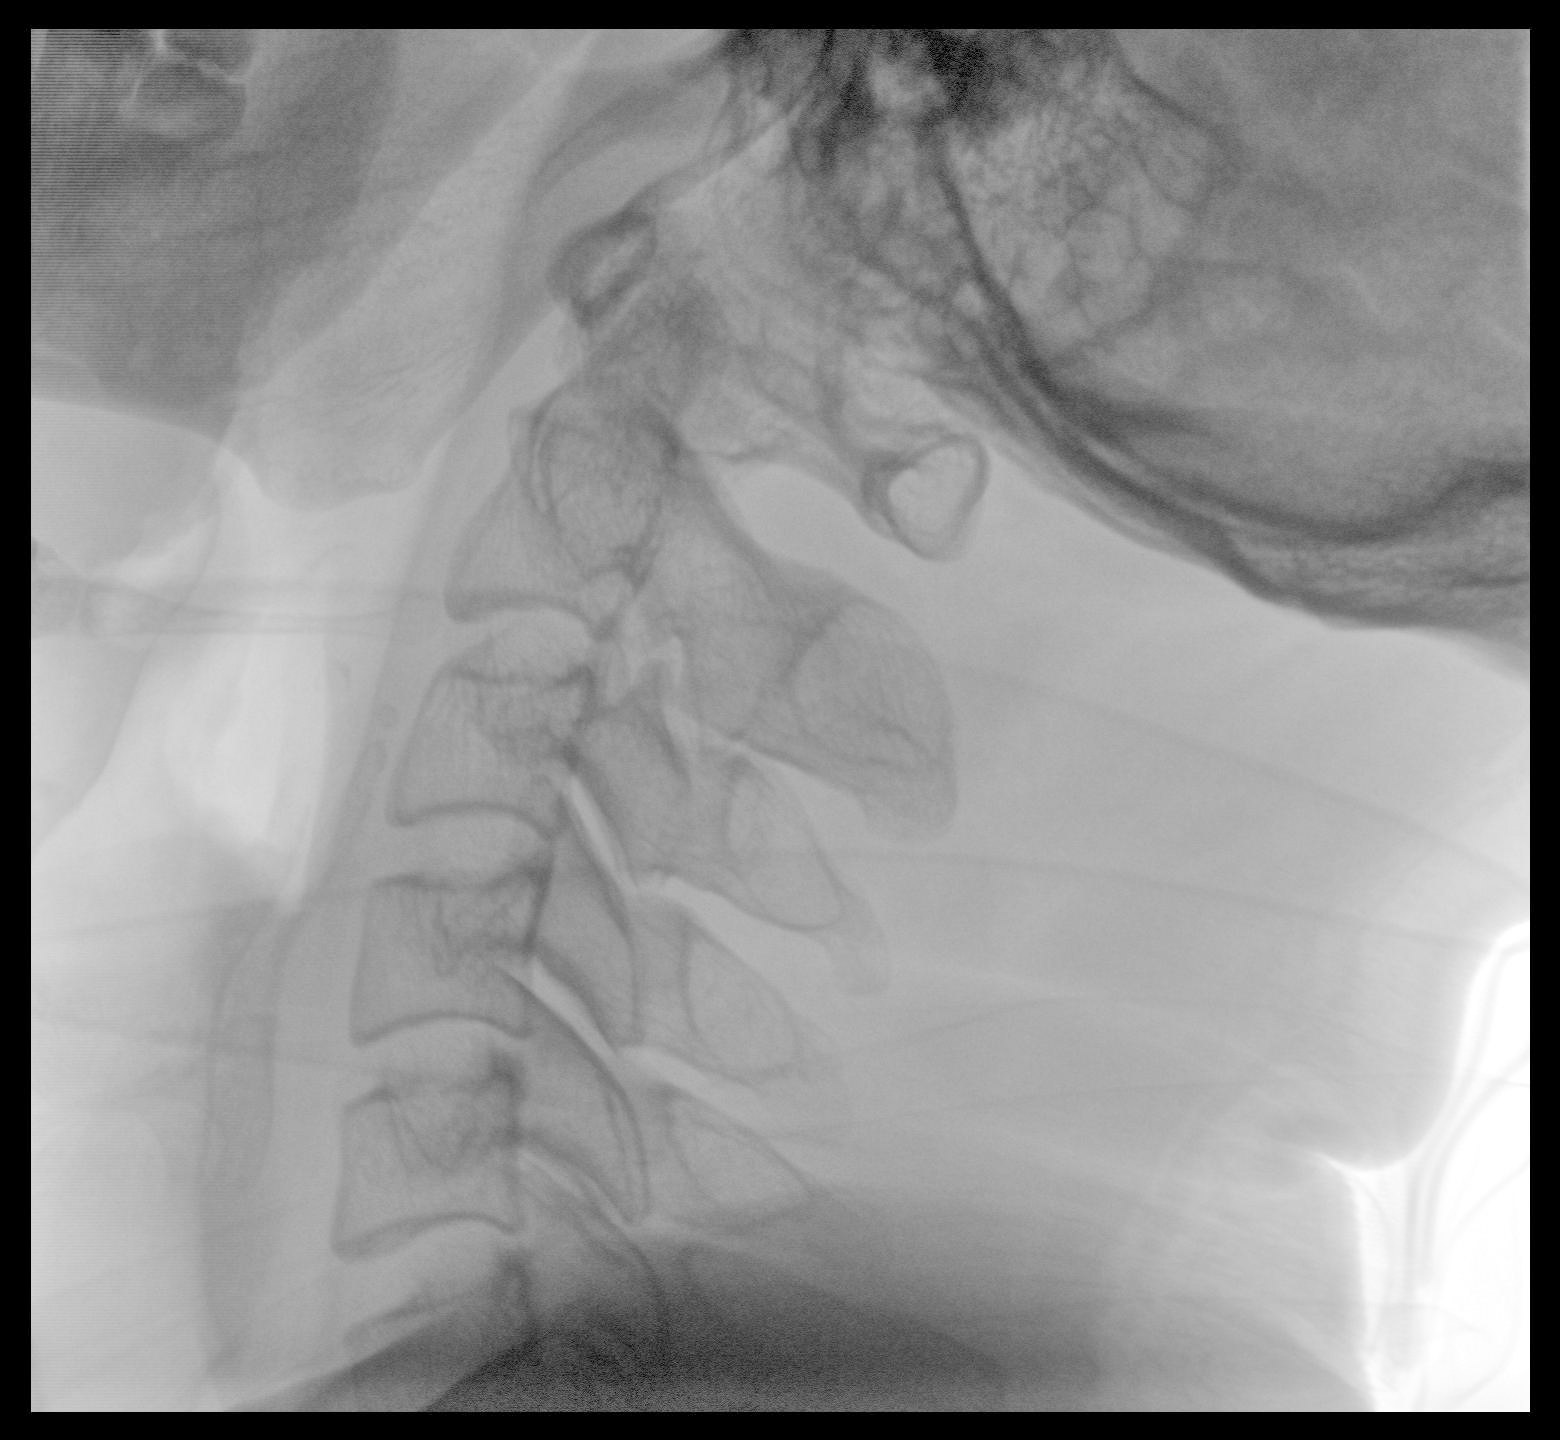

PLX118F-Plus配備了兩種平板尺寸,大尺寸動(dòng)態(tài)平板探測(cè)器成像面積較傳統(tǒng)平板探測(cè)器提升了25%以上,在視野需求大的手術(shù)中,便于醫(yī)生更好定位病灶點(diǎn),規(guī)劃手術(shù)方案,減少因視野范圍不足而多次透視、點(diǎn)片造成的不便。